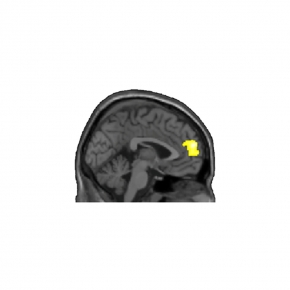

© Andry Andrianarivelo et Peter Vanhoutte - Laboratoire Neuroscience Paris-Seine (CNRS/Sorbonne Université/Inserm)